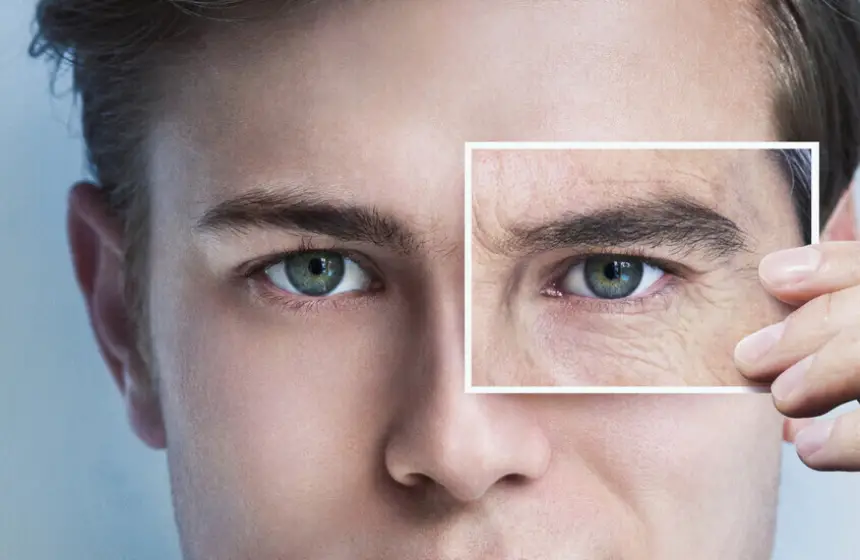

9 أعراض قد تكون من العلامات المبكرة لسرطان الرئة

يعد سرطان الرئة من أكثر السرطانات شيوعا بين الرجال والنساء على حد سواء، حيث ترتبط أسبابه بشكل وثيق بعوامل مثل التدخين، وتلوث الهواء، والتعرض للمواد السامة.

وتشير بيانات إلى أن حالات الإصابة والوفيات بسرطان الرئة تسجّل ارتفاعا ملحوظا في العديد من الدول، مما يفرض تحديات متزايدة على الأنظمة الصحية ويعيد فتح النقاش حول أهمية الوقاية والكشف المبكر.

وقالت الدكتورة جيني ماسنجر، استشارية أمراض الجهاز التنفسي والطب العام: "التدخين هو السبب الرئيسي للإصابة بسرطان الرئة، لكن يمكن أيضا أن تكون له أسباب جينية، إلى جانب التلوث، والسمنة، والتعرض للمواد الكيميائية في أماكن العمل".

وغالبا ما يشخص سرطان الرئة باستعمال التصوير المقطعي للصدر، كما أن له أعراضا تمكن من الكشف المبكر عن هذا المرض الخبيث.

9 أعراض لسرطان الرئة يجب عدم تجاهلها

ضيق التنفس

كشفت الدكتورة رشيل أوريت، مديرة المعلومات الصحية في مركز أبحاث السرطان بالمملكة المتحدة: "قد يكون الشعور بضيق التنفس عند القيام بأنشطة كنت تقوم بها سابقا دون مشكلة، أو في حال واجهتك صعوبة أخرى في التنفس علامة من علامات الإصابة بسرطان الرئة".

عدوى صدرية متكررة

وأشارت أوريت إلى أن العدوى الصدرية المتكررة، التي لا تزول ولا تتحسن مع العلاج، قد تكون علامة من هذا المرض الخبيث.

السعال طويل الأمد

نبهت المتحدثة ذاتها إلى أن السعال طويل الأمد، الذي لم يجدي معه العلاج، قد يكون علامة للإصابة بسرطان الرئة.

السعال المصحوب بالدم

في حال ملاحظة بقع دم، حتى ولو كانت صغيرة، في البلغم، يجب عدم تجاهل هذه الإشارة والتوجه فورا إلى الطبيب.

الشعور بالتعب دون سبب

وأوضحت أوريت أن التعب المستمر الذي لا يزول بأخذ فترات راحة، أو الشعور بالإرهاق عند القيام بأنشطة كان الفرد يقوم بها سابقا بسهولة، يستدعي الانتباه.

فقدان الوزن غير المبرر

قد يكون فقدان الوزن غير المبرر، دون تغيير في النظام الغذائي، أو مستوى النشاط البدني علامة تستوجب الانتباه إليها.

فقدان الشهية

يمكن لفقدان الشهية والرغبة في تناول الطعام أن يكون علامة تحذيرية.

الألم غير المبرر

قالت الدكتورة ماسنجر إن علامات سرطان الرئة تشمل أيضا الشعور بألم مستمر وحاد في الكتف أو الصدر.

تغيرات الصوت

ونبهت ماسنجر إلى أن التغيرات الصوتية المستمرة، كالبحة، من بين الأعراض الأقل شهرة لسرطان الرئة.